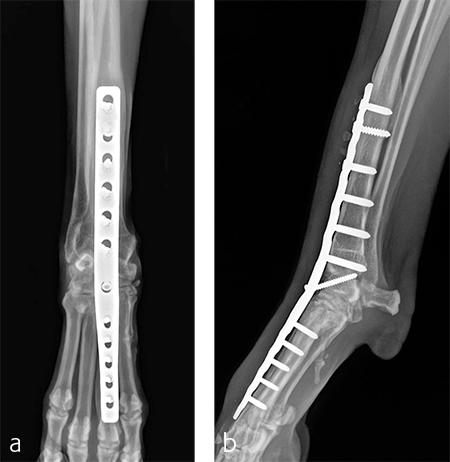

A 2.7/3.5 Pancarpal Arthrodesis was applied to the dorsal aspect of the carpus using a combination of locking and cortical screws. A 2.7 mm cortical screw was used to attach the plate to the radiocarpal bone. Five 2.7 mm locking screws were used to attach the plate to the 3rd metacarpal bone. Five 3.5 mm locking screws and one 3.5 mm cortical screw were used to attach the plate to the dorsal surface of the radius. A combination of locking and cortical screws was used to provide compression (cortical screw placed in eccentric position to provide compression across the radiocarpal joint) and achieve excellent stability and limb alignment. The incision was closed in routine fashion.

Postoperative radiographs revealed proper joint orientation and compression of the multiple antebrachiocarpal joint levels (Fig 5). Implant placement was considered excellent.